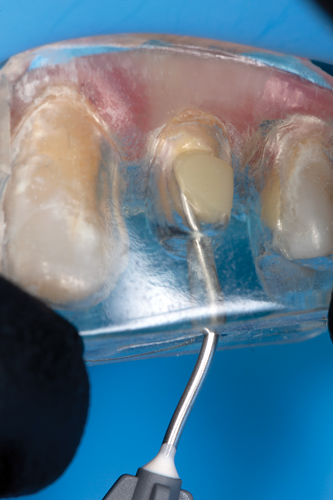

After completion of the endodontic treatment and crown lengthening to develop an ideal ferrule effect (Figure 3 through Figure 5) a diagnostic wax-up was fabricated to an ideal coronal preparation geometric shape, dimension, and height for the anticipated final composite core buildup (Figure 6). A clear polyvinyl siloxane (PVS) impression material was injected into a nonperforated tray, placed over the diagnostic wax-up, and then put into a pressure pot with cold water for 5 minutes. This procedure is aimed at reducing the potential for the formation of voids and bubbles in the impression material (Figure 7 and Figure 8). A small opening was made above the tooth to be restored using a tapered diamond bur (6847) (Figure 9). It is important to clean the internal surfaces with a microbrush to prevent silicone debris from integrating into the flowable material. Prior to the restorative procedure, a diagnostic wax-up was fabricated to the anticipated extracoronal contours for development of the final crown (Figure 10).

The clear silicone matrix was placed over the posterior segment of the maxillary arch, and an opacious A2-shaded injectable flowable universal resin composite was injected through a small opening above the preparation and fiber post (Figure 20 and Figure 21). The resin composite was cured through the clear resin matrix on the incisal, facial, and lingual aspects for 40 seconds each. Upon removal of the matrix, the excess polymerized composite resin was removed with a #12 scalpel blade, and the incisal sprue was removed using a tapered diamond finishing bur. A round, tapered diamond bur was used to establish the gingival margin (Figure 22) and a needle-shaped finishing bur was used to complete the finishing of the preparation.

Fig 3. After endodontic treatment, crown lengthening was performed to develop an ideal ferrule effect.

Figure 3

Fig 4. An adequate collar effect of 2 mm of sound tooth structure would provide an anti-rotational feature for the stability of the crown.

Figure 4

Fig 5. Buccal view of optimal ferrule effect with a healthy biological framework.

Figure 5

Fig 20. The clear silicone matrix was placed over the posterior segment of the maxillary arch, and flowable resin composite was injected through a small opening above the preparation and fiber post.

Figure 20

Fig 21. During the injection process, the tip was removed slowly while injecting to prevent the incorporation of air bubbles.

Figure 21